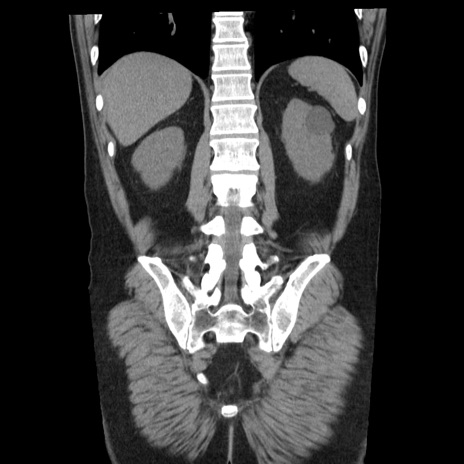

症例29(冠状断像)

【症例】40歳代男性

【現病歴】2日前から胃痛あり。徐々に周期的な激痛に変化した。本日になっても激痛があるため受診。

【身体所見】意識清明、BT 38-39℃台あり、腹部:膨満、やや硬、右下腹部に圧痛あり。

【データ】WBC 8500、CRP 23.26